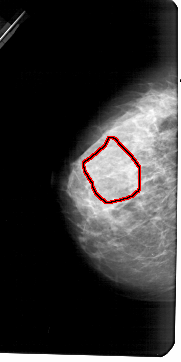

A_1183_1.LEFT_CC

LEFT_CC LINES 5416 PIXELS_PER_LINE 2701 BITS_PER_PIXEL 12 RESOLUTION 43.5 OVERLAY

FILE: A_1183_1.LEFT_CC.OVERLAY

TOTAL_ABNORMALITIES 1

ABNORMALITY 1

LESION_TYPE CALCIFICATION TYPE PUNCTATE DISTRIBUTION REGIONAL

ASSESSMENT 4

SUBTLETY 1

PATHOLOGY MALIGNANT

TOTAL_OUTLINES 1

BOUNDARY